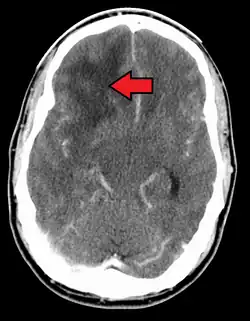

When viewed with MRI, glioblastomas often appear as ring-enhancing lesions. The appearance is not specific, however, as other lesions such as abscess, metastasis, tumefactive multiple sclerosis, and other entities may have a similar appearance.[61] Definitive diagnosis of a suspected GBM on CT or MRI requires a stereotactic biopsy or a craniotomy with tumor resection and pathologic confirmation. Because the tumor grade is based upon the most malignant portion of the tumor, biopsy or subtotal tumor resection can result in undergrading of the lesion. Imaging of tumor blood flow using perfusion MRI and measuring tumor metabolite concentration with MR spectroscopy may add diagnostic value to standard MRI in select cases by showing increased relative cerebral blood volume and increased choline peak, respectively, but pathology remains the gold standard for diagnosis and molecular characterization.